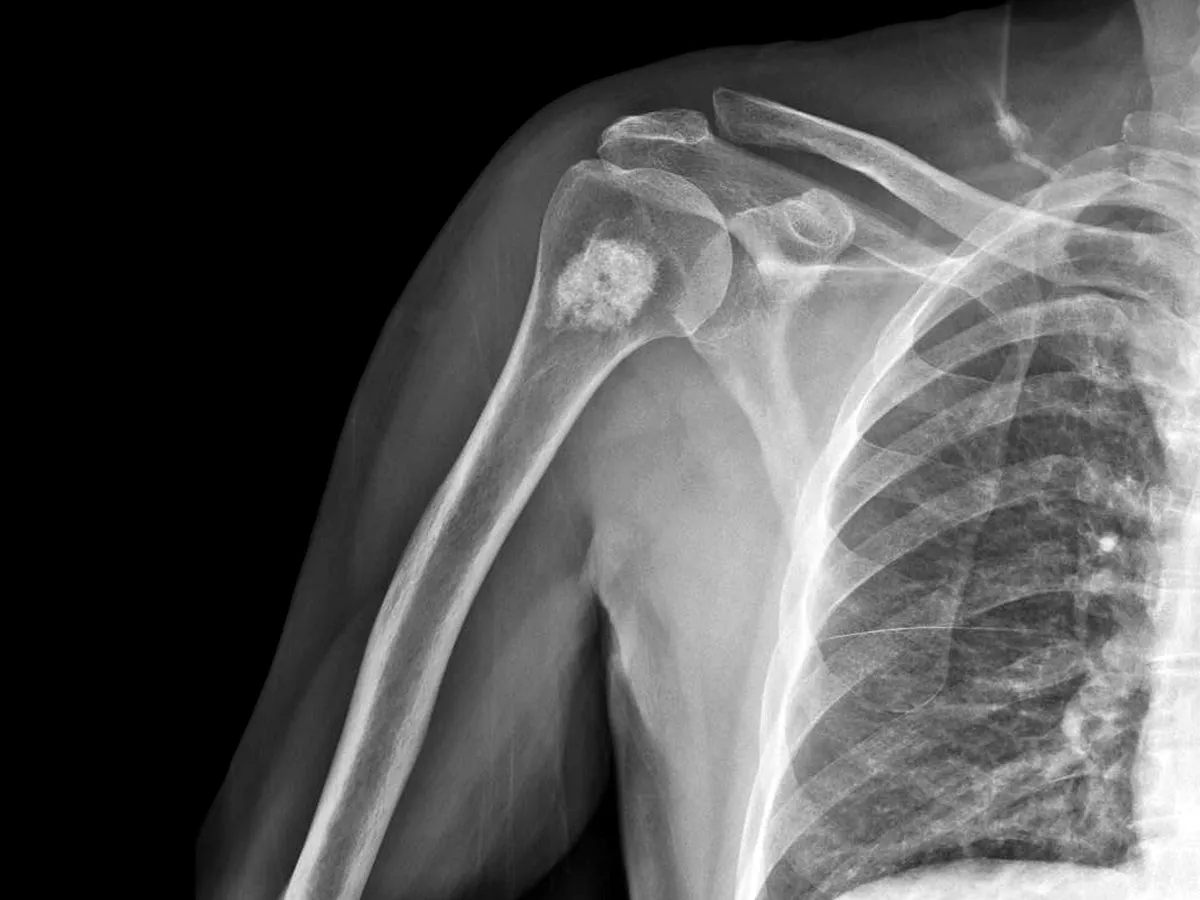

Złamania patologiczne: Kiedy kość pęka bez wyraźnego powodu?

Przerzuty do kości osłabiają jej strukturę, czyniąc ją niezwykle podatną na uszkodzenia. W efekcie może dojść do tzw. złamań patologicznych. Są to złamania, które występują przy niewielkim urazie (np. upadek z wysokości własnego ciała) lub nawet samoistnie, bez żadnej wyraźnej przyczyny. Pojawienie się takiego złamania jest zawsze alarmującym sygnałem i wymaga pilnej diagnostyki w kierunku przerzutów.

Od RTG po PET-CT: Jakie badania obrazowe potwierdzają diagnozę?

Diagnostyka przerzutów do kości opiera się głównie na badaniach obrazowych. Najczęściej wykorzystywane są:

- RTG (zdjęcie rentgenowskie): Jest to badanie podstawowe, często wykonywane jako pierwsze, choć może nie wykrywać małych zmian.